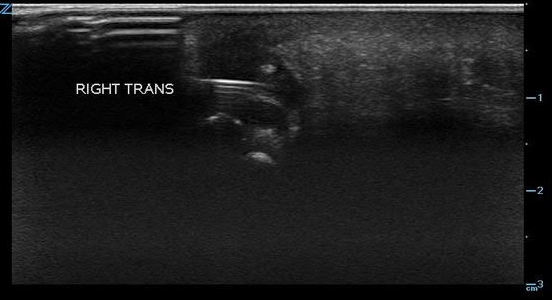

- The area is scanned throughout its entirety in search for a hyperechoic object in both the sagittal and transverse planes as it can sometimes be much easier to visualize an object in one plane but not the other. Be aware of possible surrounding tissue inflammation or abscess.

- Visualization of foreign bodies is easiest when the probe is parallel to the object and therefore attempts should be made to visualize the area in question from many angles if possible.

- Once a foreign body is localized, the depth from the skin can be measured as well as the size of the object.